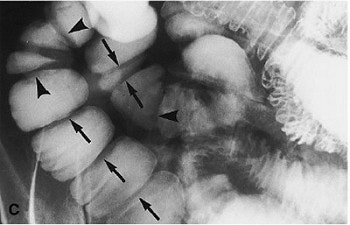

![]() ![]() |

Overhead view (A) shows three abnormal jejunal loops. Four broad-based strictures with lumps are seen in loop 2 (arrows). Compression spot view of loops 1-2 (B). Marked luminal narrowing in two of the four strictures in loop 2 (arrows) is seen with a resultant life-saver or bagel-like configuration. Compression spot view of loop 3 (C). Multiple ring or diaphragm-like strictures (arrows) and broader-based strictures (arrowheads) are evident. Images courtesy of the Canadian Association of Radiologists (Abdominal Imaging, 1998; 23:40-44).